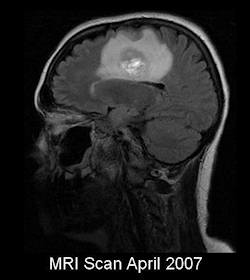

March 2008 - Visit to the Eden Project in Cornwall. This is our first night away from home together for more than a year.

May 2008 - A dream realised for us both - a week's holiday in Italy in a hotel overlooking the Bay of Naples and Mount Vesuvius. Amazingly Kath manages to walk all round Pompeii on a very hot day - and even survives being hurled around in a bus piloted down twisty roads by a crazy Italian driver.

August 8 2008 - After twenty years together we finally get married. Just close family and a couple of friends present. The date 08.08.08 is chosen because it was supposed to be lucky.

December 2008 - A scan reveals the tumour has come back and is affecting her left side - including her face. Her left leg is failing her occasionally, causing her to fall. Now seems to have lost much of the use of her left arm and her speech has become slightly slurred.